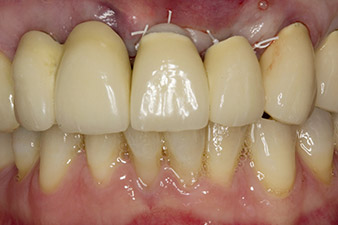

Nach primärer Abheilung werden die Weichgewebe mithilfe der basal unterfütterten Brücke ausgeformt. Zwei Monate später erfolgt die Freilegung mit einem leicht palatinal gelegten Kieferkammschnitt (Abb. 2).

Um den parodontalen Knochenverlust auszugleichen und ein ästhetisches Ergebnis zu erreichen, wird die Implantation mit gesteuerter Knochenregeneration mit xenogenem Ersatzmaterial und einer Kollagenmembran kombiniert (Abb. 5 und 6).

Bei Implantatversorgungen in der ästhetisch sensiblen Oberkieferfront sind zahlreiche Faktoren zu berücksichtigen (1). Dazu gehören Design und Material der Prothetik (2) sowie Quantität und Qualität der periimplantären Gewebe. Hinzu kommen Fragen der Einheilung, der temporären Phase (3) und der Art der Fixierung (4).

Im Fallbeispiel wurde die Situation im ersten Eingriff mit einem Implantat an Position 22 gelöst, und einem weiteren an der Position des im weiteren Verlauf extrahierten Zahnes 23. Das zweite Implantat folgt nach Osseointegration von Implantat 22. Die umgearbeitete Brücke wurde bis zur Einheilung von Implantat 23 und der Abformung für den definitiven Zahnersatz wieder eingegliedert. Vorteile dieses abgestuften Vorgehens sind eine sichere Belastbarkeit der Implantate und gut ausgereifte Hart- und Weichgewebe (5).